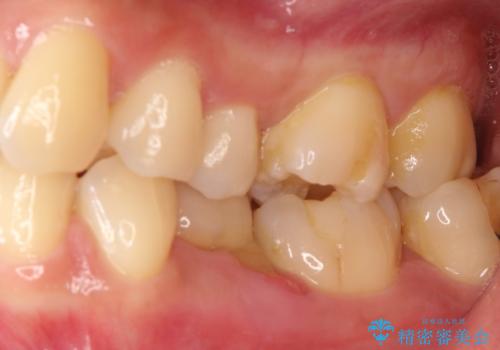

奥歯が痛い。乳歯を抜歯し、ブリッジによる咬合回復。

インプラントは希望されなかったため、ブリッジにて治療を行っております。

欠損補綴に対し、インプラントは有効な手段ですが比較的高額で、手術を伴います。

患者様によってはブリッジを選択される方もいらっしゃいます。